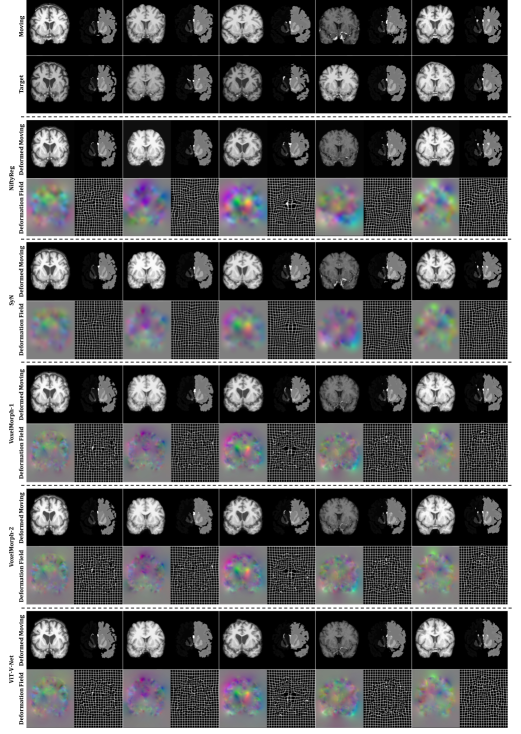

fig_quali

We demonstrate our method on the task of brain MRI registration. We used an in-house dataset that consists of 260 T1–weighted brain MRI scans. The dataset was split into 182, 26, and 52 (7:1:2) volumes for training, validation, and test sets. Each image volume was randomly matched to two other volumes to form four pairs of and , resulting in 768, 104, and 208 image pairs. Standard pre-processing steps for structural brain MRI, including skull stripping, resampling, and affine transformation were performed using FreeSurfer [Fischl(2012)]. Then, the resulting volumes were cropped to an equal size of . Label maps including 29 anatomical structures were obtained using FreeSurfer for evaluation. The proposed method was compared in terms of Dice score [Dice(1945)] to Symmetric Normalization (SyN)111Implementation of SyN was obtained from \urlhttps://github.com/ANTsX/ANTsPy [Avants et al.(2008)Avants, Epstein, Grossman, and Gee], NiftyReg222Implementation of NiftyReg was obtained from \urlhttps://www.ucl.ac.uk/medical-image-computing [Modat et al.(2010)], and a learning-based method, VoxelMorph333Implementation of VoxelMorph was obtained from \urlhttp://voxelmorph.csail.mit.edu-1 and -2 [Balakrishnan et al.(2018)Balakrishnan, Zhao, Sabuncu, Guttag, and Dalca]. The regularization parameter, , was set to be 0.02, which was reported in [Balakrishnan et al.(2018)Balakrishnan, Zhao, Sabuncu, Guttag, and Dalca] as an optimal value for VoxelMorph. The method was implemented using PyTorch [Paszke et al.(2019)]. Detailed hyperparameter settings for training are shown in Appendix C. Qualitative results, and Dice scores are shown in Table 1 and Fig. LABEL:fig_quali. As visible from the results, the proposed ViT-V-Net yielded a significant gain of in Dice performance (-values are shown in Table. 4) compared to the others. We also noticed that ViT-V-Net reached lower loss values and had higher validation Dice scores during training (see Fig. LABEL:fig_curve in Appendix D). In conclusion, the proposed ViT-based architecture achieved superior performance than the top-performing registration methods, demonstrating the effectiveness of ViT-V-Net.